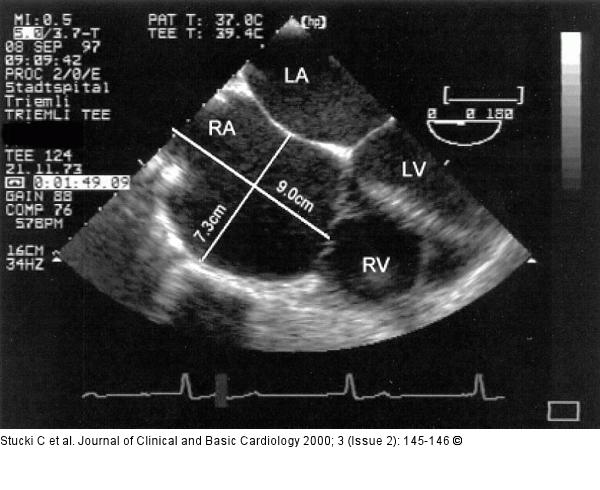

Figure/Graphic 2: Emery-Dreifuss Muskeldystrophie - Kardiopathie Transesophageal echocardiogram showing a grossly dilated right atrium and a moderately dilated left atrium without any active contraction |

Transesophageal echocardiogram showing a grossly dilated right atrium and a moderately dilated left atrium without any active contraction |